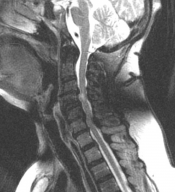

Verminderd gevoel in beide armen na een val. Wat is de diagnose? Gepost op 3 juli 20173 juli 2017 door netwerkvsseh What’s the Diagnosis? @emdaily.cooperhealth.org Dit delen: Delen op X (Opent in een nieuw venster) X Share op Facebook (Opent in een nieuw venster) Facebook Delen op LinkedIn (Opent in een nieuw venster) LinkedIn E-mail een link naar een vriend (Opent in een nieuw venster) E-mail Afdrukken (Opent in een nieuw venster) Print Vind-ik-leuk Aan het laden... Gerelateerd